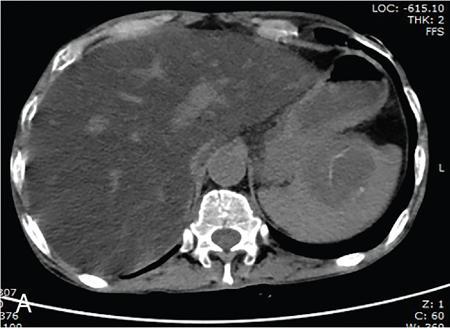

Vijay Kumar K.R. CONGENITAL SPLENIC ABNORMALITIES A multitude of variants and pathologies affect the spleen and it is pertinent for a radiologist to be aware of the common imaging appearances of the same. The spleen begins to develop in the fifth week of gestation from a mass of mesenchymal cells that condense between the two leaves of the dorsal mesogastrium. Several such aggregates fuse to form the lobulated embryonic spleen. The spleen is translocated to the upper left side of the abdominal cavity due to rotation of the stomach and differential growth of the dorsal mesogastrium. The mesogastrium fuses with the peritoneum over the left kidney and forms the splenorenal ligament. The lienorenal ligament fuses dorsally and the splenic artery courses behind the peritoneum as it enters the splenorenal ligament. The portion of dorsal mesentery between the stomach and spleen forms gastrosplenic ligament. Differentiated mesenchymal cells form the parenchyma, connective tissue and capsule of the spleen. The foetal spleen shows lobulations, which normally disappear before birth. However, they may persist along the medial part of the spleen. Sometimes a persisting portion of the spleen may extend medially and anteriorly over the upper pole of the left kidney. It may be mistaken for a space-occupying lesion arising from the kidney. Rarely it may extend posterior to the upper pole of the left kidney, displacing it anteriorly (Fig. 9.22.1.1). The notches and clefts along the superior borders are vestiges of the grooves that initially separated the foetal lobules. They may be 2–3 cm deep. They may mimic a splenic laceration in a patient with abdominal trauma, and the embedded peritoneum at the waist may simulate splenic infarction or haematoma. Hence caution should be exercised. A normal spleen which does not have a fixed ligamentous attachment can change position within the abdomen and is hence known as a wandering spleen. The spleen is normally anchored by the gastrosplenic and lienorenal ligament. Absence or weakness of one or more ligaments that affix the spleen. The spleen with its vascular pedicle as the sole attachment can become a hypermobile intraperitoneal organ. Rarely, the spleen may be normal in position with a wandering accessory spleen. Pregnancy (due to hormonal effects), prune belly syndrome, splenic cysts, malaria, Hodgkin’s disease and lymphangioma. Some of the affected patients may be asymptomatic and diagnosis may be incidental. Clinically it presents as a mobile, palpable, notched mass. Pressure on the vascular pedicle or torsion causes symptoms such as acute abdominal pain, nausea and vomiting. Torsion involving the tail of the pancreas may present as pancreatitis. Confirms the absence of spleen in the left upper quadrant of abdomen with identification of splenic tissue at an ectopic site. Power Doppler, colour Doppler and duplex sonography allow for the identification of blood flow in the splenic vessels and parenchyma. Intermittent torsion may be responsible for an enlarged spleen. Pathognomonic feature of wandering spleen is absence of the spleen in the upper abdominal cavity and presence of a well-demarcated, homogeneously enhancing mass of soft tissue in the pelvis or abdomen. Sometimes a wandering accessory spleen can be visualized as a long vascular pedicle connecting a small mass to the splenic vessels (‘jokari sign’). It can locate ectopic splenic tissue and can also indicate the viability of the tissue. Splenic vessel anatomy can be well demonstrated. 99mTc-sulphur colloid scintigraphy and heat denatured 99mTc-labelled red blood cell imaging provide useful information regarding size and location of splenic tissue. Torsion is indicated by lack of tracer activity in a previously demonstrated wandering spleen. Twisting and torsion of splenic artery can be demonstrated by celiac arteriography. The venous phase may demonstrate splenic vein obstruction with collateral circulation and varices. A congenital focus of normal splenic tissue that is separate from the main body of the spleen is known as an accessory spleen. It results from the failure of fusion of some embryonic splenic buds within the dorsal mesogastrium. Its incidence varies from 10% to 30% on autopsy examinations. They vary from a few millimetres to several centimetres in diameter. They most commonly are found around the splenic hilum. The second most common location is the pancreatic tail. They can also be found in the stomach wall, omentum, mesentery, large bowel and scrotum. Reveals a round or oval mass of tissue around the splenic hilum that is isoechoic with the main spleen. On noncontrast images they are isodense to the main spleen. CECT reveals serpiginous enhancement on arterial phase followed by homogeneous enhancement on venous phase-like spleen (Fig. 9.22.1.2). Accessory spleen is mildly hypointense to the spleen on T1 images and isointense on T2 images. Contrast administration reveals enhancement similar to that of spleen on the arterial, portal and late phases. It is isointense to spleen on DWI images with similar ADC values. 99mTc-sulphur colloid scintigraphy and heat denatured 99mTc-labelled red blood cell imaging show functional uptake in splenic tissue and differentiate splenule from other masses. PET CT-FDG avid mass can mimic tumour. Surgical resection is the preferred mode of treatment in the background of hypersplenism or lymphoma. It is characterized by an ectopic splenic tissue or an abnormal connection between the gonad and the spleen. The left side is more commonly involved than the right side. The accepted theory is that splenic gonadal fusion occurs due to abnormal attachment of the splenic anlage in the left dorsal mesogastrium with the left urogenital fold, during the fifth to eighth weeks of gestation. It has a higher male preponderance and can interfere with left testicular descent and closure of processus vaginalis. It commonly presents as inguinal hernia and cryptorchidism. The spleen and gonad are attached by a fibrous or splenic cord across the peritoneal cavity. It is associated with limb defect syndrome, cleft palate, micrognathia, anal anomalies, craniosynostosis, spina bifida, cardiac malformations, thoracic malformations and diaphragmatic hernias. This is not associated with congenital anomalies. Shows a well-defined scrotal mass with echotexture similar to that of spleen. Confirms splenic tissue in inguinal or scrotal area. It is characterized by the absence of spleen with duplication of right-sided structures. (Right isomerism). It has a slight male preponderance with an incidence of 1 in 40,000 live births. It has a poor prognosis due to its high association with congenital cardiac abnormalities (Fig. 9.22.1.3). It is of uncertain aetiology, and maybe associated with the mutations of CFC1 gene, SHROOM3 gene etc. Delayed development of embryonic curvature can be another cause. It is also theorized that it can be caused due to vascular compromise by pressure on splenic blood supply from adjacent structures. Splenectomy – Usually has a surgical history and is not accompanied by associated anomalies. It is a heterotaxy syndrome associated with multiple spleens and duplication of left-sided structures. (Left isomerism). It has an equal gender predilection with a slightly higher female preponderance. It has a fairly better prognosis than asplenia and is associated with a lesser incidence of cardiovascular anomalies (Fig. 9.22.1.4). It is of uncertain aetiology, and maybe associated with the mutations of CFC1 gene, SHROOM3 gene etc. Accelerated development of embryonic curvature can be another cause. SPLENIC INFECTION AND ABSCESS The infection of the spleen can show three patterns. Fungal and granulomatous infections usually present with multiple micronodules. A pyogenic abscess usually manifest as a solitary lesion. Imaging of diseases causing splenic nodules is never the sole basis for diagnosis. The clinical presentation and laboratory testing (tumour markers, tuberculosis testing and bone marrow biopsy) help in establishing an accurate diagnosis. The imaging findings are nonspecific and the nodules may vary in size from a few millimetres up to 2 cm in diameter. They maybe hypoechoic on ultrasound and hypoattenuating on CT. They are of low signal intensity on T1-weighted sequences and vary from hypointense to hyperintense on the T2-weighted sequences. The nodules show no enhancement or show ring enhancement after contrast study. Healed granulomas are seen as scattered, discrete, small calcifications in an otherwise normal spleen. With increasing number of immunocompromised patients, such as oncology patients undergoing aggressive chemotherapy, critically ill patients in intensive care units, injection drug abusers, and HIV-infected patients, there is rise in the incidence of splenic abscess. For splenic abscess to develop, it may require the presence of bacteremia (sepsis and septic emboli) and altered splenic architecture, which is caused secondary to a haematoma, infarct, or sickle cell disease. Abscesses can also develop from the extension of infection from adjacent organs, like in cases of infected pancreatitis and perinephric abscess, which are less common. In about 20% of cases, cause or source could not be discovered. Abscesses can be unilocular or multilocular, solitary or multiple, depending on the causative organisms and patient’s immunity. Mortality ranges from 15% in otherwise healthy patients with unilocular splenic abscess to 80% in immunocompromised patients with multiple abscesses. Abscesses which are multilocular, gas-containing or due to gram-negative bacillus show poor prognosis. A pyogenic abscess is usually solitary, unilocular/multilocular, but it can also be multifocal. These are uncommon and are reported in 0.14%–0.70% of large autopsy series. Most common presentation is fever (92%), left upper abdominal pain (77%) and leucocytosis (66%). Other symptoms are left pleural effusion and splenomegaly. It can be solitary or multiple, unilocular or multilocular. The appearance of splenic abscess depends on the stage of development. In the early stages of the disease, an abscess appears as an ill-defined mass later developing into a complex collection with septations, debris and sometimes gas. In later stages, after a capsule is developed, the lesion becomes well defined. Left pleural effusion is seen in around 42% of cases. Left lung base atelectasis in 20% of cases and splenomegaly is seen. Abscess with air can be identified based on the presence of extraluminal gas or air–fluid levels in the left upper quadrant. Ultrasonography has a sensitivity of 75%–98% in detecting splenic abscess. This is a very useful modality in patients who are bedridden, with renal impairment and for assessment of small splenic lesions (Fig. 9.22.2.1). Ill-defined hypoechoic mass mimicking a mass is seen in the early phase of the infection and a complex mass with internal septations, debris, rarely acoustic shadowing caused by gas is seen in later stages. The capsule appears as a thin hyperechoic rim. It is noninvasive, speedy, and a modality with high sensitivity (92%–98%). It helps in differentiating unilocular from multilocular lesions and, gives exact anatomical localization and information about perisplenic area, which later helps in planning-guided management procedures. An abscess is seen as a hypodense collection or complex cystic lesion with enhancing rim on the postcontrast study (Fig. 9.22.2.2). CT may help in identifying concurrent areas of infection and, thus, the source of infection. On CT, an abscess may look similar to an infarct, haematoma, or neoplasm. An infarct lacks mass effect, unlike abscess or tumour (Fig. 9.22.2.3). The presence of gas within the lesion is diagnostic of abscess; however, this finding is rare. Splenic abscesses show low signal on T1-weighted images and high signal on T2-weighted images compared with the normal spleen. Minimal to intense peripheral enhancement is seen after IV administration of gadolinium. But MRI is not routinely done, as many patients are clinically unstable. This plays a limited role in the detection and localization of splenic abscess. A nonspecific filling defect is seen on a 99mTc-sulphur colloid scan within spleen if the size is more than 2 cm in diameter. Normal inherent splenic activity on 67Ga scans and 111In-labelled leukocytes scans obscures any kind of inflammatory focus in the spleen, giving rise to false-negative examination. 67Ga scans are nonspecific as tracer uptake can be seen in neoplastic conditions such as lymphoma. Detection and characterization of the abscess are better done if 99mTc-sulphur colloid scan is done prior to 111In-labelled leukocytes scan. FDG PET/CT can also detect the site of infection but not used in the diagnosis of splenic abscess. Early diagnosis of an abscess is prompted for a better outcome. Based on laboratory findings, appropriate antibiotic therapy initiated. USG or CT-guided percutaneous aspiration is tried if the abscess is less than 5 cm in size, and for larger abscesses, percutaneous drainage procedures are done preserving the spleen. Splenectomy is reserved for complicated infections. Fungal abscesses are usually seen in immunocompromised patients with neutropenia such as patients with acquired immunodeficiency syndrome (AIDS), on chemotherapy and immune suppressive agents, and with lymphoproliferative disorders. With the advent of aggressive chemotherapy, the incidence of splenic fungal infections has increased. Approximately 7% of patients with acute leukaemia have hepatosplenic fungal infections. Multiple microabscesses are common. Hepatosplenic candidiasis lesions are very small, and before the advent of CT and MRI, their detection was too difficult. They measure in the range of 5–10 mm in diameter; however, they may be even miliary (<5 mm). Infections are mostly caused by candida species. Other organisms are aspergillus, Histoplasma and Cryptococcus. Imaging characteristics depend on the stage and severity of neutropenia. In cases of chronic disseminated infections with poor neutrophil counts, sometimes lesions are not visible as the host fails to produce an immune response. Lesions become apparent once neutrophil counts improve. Patients presenting with fever and splenomegaly are not improving on conventional antibiotic therapy, and with associated immunocompromised status, fungal infections are to be considered. No single imaging is specific or sensitive in establishing the diagnosis. Serial imaging is needed to detect hepatosplenic involvement; however, tissue diagnosis is the gold standard. Four different patterns are seen in hepatic candidiasis. Multiple, small, homogeneous hypoechoic nodules are the most common finding. Less commonly wheel-within-a-wheel appearance (i.e. the target sign) is seen in the early stage of infection. The first wheel is the peripheral hypoechoic zone of fibrosis and an echogenic second wheel of inflammatory cells around a central hypoechoic nidus containing necrosis and fungal elements. Later these lesions evolve into Bull’s eye lesion where there is a central echogenic focus surrounded by a hypoechoic halo. Lesions become small and hyperechoic with various degrees of posterior acoustic shadowing, with or without calcification, or they may even disappear later in the course of the infection. Splenic nodules are hypodense lesions measuring in the range of 5–10 mm. Only 30% of cases are detected in noncontrast studies. They often have low attenuation, although there can be a focus of high attenuation or a ‘wheel-within-a-wheel’ pattern. Peripheral ring of enhancement is noted in around 70% of cases in the arterial phase of CT, and it is said to disappear on the portal venous phase. There is no significant difference in the detection of the lesions between arterial and portal venous phases of contrast studies. MRI is said to be the investigation of choice for diagnosis of hepatosplenic candidiasis and is superior to CT and USG, especially when short-time inversion recovery sequence is used. MR imaging is also used to monitor the response to antifungal therapy. Based on MRI findings different phases of hepatosplenic candidiasis are described. Lesions are small, measuring less than 1 cm in diameter. They show mildly hypointense on the T1-weighted images and markedly hyperintense on the T2-weighted images. In 2 weeks to 3 months, acute lesions are transformed into subacute lesions. The lesions reveal mildly increased signal on both T1- and T2-weighted sequences. On all sequences, a peripheral ring of very low signal intensity is seen. Following the gadolinium administration, the central region of the lesions show enhancement; however, the peripheral ring continues to have low signal intensity, making them more obvious. It takes from 3 months to more than 1 year for the healed fungal foci composed of fibrous tissue of differing densities and degrees of vascularization to appear on MRI. The lesions measure 1–3 cm, become irregular, and the central area disappears. Chronic healed fungal abscesses have low signal intensity on T1-weighted images and are isointense to mildly hyperintense on T2-weighted images. No perilesional dark ring is noted. These lesions are moderately hypointense on early postgadolinium images and minimally hypointense on delayed postgadolinium images. Mycobacterial tuberculosis infections are mainly seen in immunocompromised patients. Spleen involvement is seen in disseminated, miliary infection in about 80%–100% of autopsy cases; however, it is documented less on imaging. Splenic tuberculosis is seen in the form of nodules measuring ∼ 0.2 and 1 cm in diameter. The macronodular form is very rare (Fig. 9.22.2.4). Hypoechoic pattern is seen. Hypoattenuating nodules with lymphadenopathy noted. Depending on the different stages of the tubercular process, intensities on T1- and T2-weighted images vary. On contrast-enhanced T1-weighted images, lesions most often show peripheral enhancement less commonly gradual peripheral enhancement with complete filling is noted. It is also called as Mycobacterium intracellulare infections. These are also typically seen in immunocompromised patients. Splenomegaly with multiple, low attenuation nodules is seen. Associated findings such as hepatosplenomegaly, diffuse jejunal wall thickening and enlarged lymph nodes are seen. Lymph nodal involvement is homogeneous as opposed to Mycobacterium tuberculosis infections. Focal splenic or hepatic lesions are noted in about 30% of patients with HIV who are infected with M. tuberculosis but are rarely noted in those infected with M. avium intracellulare. Marked splenomegaly is more common in M. avium intracellulare than in M. tuberculosis infection. It is a common opportunistic infection in patients with HIV. Extra pulmonary involvement manifested in the form of necrotizing granulomas. Spleen involvement is an incidental finding. When treated the nodules may enlarge and become progressively calcified in a rim like or punctate fashion. Disseminated infection can show punctate calcification in adrenal glands, pleural or peritoneal effusions, that subsequently calcify. Splenomegaly with small hypoechoic lesions with cystic components or tiny, highly reflective, nonshadowing foci or calcified granulomas. The nodules are hypodense. Calcified granulomas are seen in later stages. This is a self-limited disease caused by bartonellae henselae. Hepatosplenic involvement is rare. This disease is to be considered when a patient presents with abdominal pain, fever of unknown origin, and multiple hypodense lesions in the liver and spleen. It is also called as echinococcosis, a disease seen in endemic regions and in patients emigrated from endemic areas. The causative organism is a zoonotic tapeworm echinococcus granulosus. The most commonly involved organs are the liver, lung, peritoneum, kidney, brain, mediastinum and heart. Spleen is rarely primarily involved. Spleen is involved in approximately 2% of cases of abdominal hydatidosis. Spleen involvement is seen in case of an extensive abdominal hydatidosis, like after the rupture of liver hydatid cyst or in cases of systemic dissemination of infection. Larvae of the tapeworm incite an inflammatory response after its entry into the target tissue in the host where it forms a hydatid cysts consisting of three layers. Peri cyst is an outer layer of modified host cells forming a dense and fibrous layer. The middle layer laminated layer and an inner germinal layer made up of daughter cysts, also called as brood capsules. Scolices develop in the brood capsules. The laminated and germinal layer forms the true cyst wall. After the parasites die, the cysts become inactive, may calcify, and undergo fibrosis. Patients present with abdominal pain, splenomegaly and fever. The diagnosis is to be suspected in all patients from endemic areas presenting with a splenic cyst. A World Health Organization Working Group on echinococcosis has a standardized sonographic classification of echinococcal cysts (Table 9.22.2.1). CE, cysticechinococcosis; CL, undifferentiated simple cystic lesions. Radiological appearances depend on the natural aging process of the cyst. Classic imaging characteristics are lost when the cyst becomes secondarily infected. A ring-like or curvilinear calcification noted in the left hypochondriac region. This may represent the calcification of pericyst in later stages of the disease. Ultrasound is an easy and most commonly used for evaluation of a suspected case of abdominal echinococcal disease. It is used for the diagnosis, planning the management and follow-up. Shifting of brood capsules within the cyst causes fine internal echoes, that is ‘The snowflake sign’ (hydatid sand). Detached laminated endocysts may be seen within the cysts, that is ‘The. Waterlily sign’. Mother cysts may be partially /completely filled by daughter cysts. Calcifications with posterior acoustic shadowing are seen in later stages of the disease. CT and MRI are indicated for widespread disease and complications and for planning percutaneous therapy and surgery. Complications of a hydatid cyst include compression of the adjacent structures, cyst rupture, secondary infections, anaphylaxis and fistulization to surrounding structures. A hydatid cyst may be seen as a well-defined, hypoattenuating cystic lesion with fluid-attenuation values and a distinguishable wall. CT is more sensitive for subtle wall calcification. May appear hyperdense because of debris, hydatid sand and inflammatory cells (Fig. 9.22.2.5). In CE 2 cysts, peripherally arranged daughter cysts, completely fill them other cyst. The daughter cysts show lower attenuation than the mother cyst. Type CE 3 lesions are round or oval with occasional calcification and daughter cysts. They usually show high attenuation. Type CE 4 cysts are complex masses. Intravenous contrast administration reveals enhancement of septa and cyst wall. Type CE 5 cysts are complex cystic or solid-looking lesions, and they can be partially or completely calcified. The simple cysts show low signal on the T1-weighted images and markedly hyperintense on the T2-weighted images. The rim sign which is a low signal intensity rim well seen in T2-weighted MRI images is characteristic of hydatid disease. Enhancement of septa and cyst wall is noted after the intravenous administration of gadolinium. On T1- and T2-weighted images, the maternal matrix appears hyperintense relative to the daughter cysts. The collapsed parasitic membranes may show serpent sign or snake sign, which are hypointense on all sequences. Hypointensity on T1- and T2-weighted images are seen in type CE 4 and CE 5 cysts. The imaging findings combined with the clinical, immunologic testing and epidemiologic results, usually provide the correct diagnosis. Seen in cases of tuberculosis, histoplasmosis, less commonly in Pneumocystis jirovecii pneumonia and brucellosis. These are incidental findings usually preceded by hypoattenuating microabscesses. Microabscesses heal with or without preceding regression. More than five calcifications usually represent histoplasmosis, whereas less than five represent tuberculosis. A ring-like calcification is seen in Pneumocystis carinii pneumonia. Any granulomatous infection is more likely to involve other organs such as the liver, kidneys and lymph nodes. Hydatid cysts can show ring-like or curvilinear calcification (Fig. 9.22.2.6). SPLENOMEGALY AND HYPERSPLENISM Splenomegaly is often a nonspecific finding, and there are many causes for splenomegaly. The spleen can grow into large sizes towards right iliac fossa, crossing midline. On average adult spleen measures <11 cm in length,<7 cm wide,<5 cm thick, and weighs approximately 150 g (80–300 g). The size and weight of the spleen decrease with advancing age. Spleen size is significantly influenced by the sex and body height of an individual. Chow et al. assessed 1230 healthy volunteers and found that spleen length and volume were significantly and independently associated with sex, body height and weight. Taller and heavier male individuals have larger and longer spleens. In one study the spleen length in 6% of women, and 26% of men exceeded a strict upper limit of normal of 12 cm. Rosenberg et al. established an upper limit of standard splenic length of 12 cm for girls and 13 cm for boys (≥15 years). Massive splenomegaly is defined as a spleen size greater than 18 cm, is less common and includes haematological disorders and infections (Table 9.22.3.1).